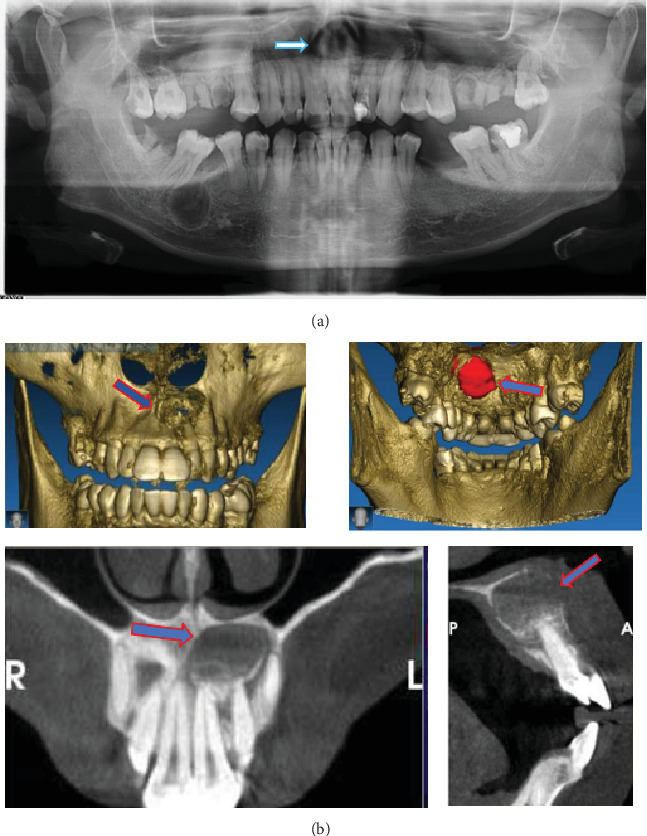

Introduction: Radicular cysts are the most common type of inflammatory cyst of the jaw. Management of radicular cysts may include cyst enucleation with apical resection. Spontaneous bone healing after cyst enucleation has been reported to occur in 73.5% of cases after 12 months. Residual cavity size was reduced 12.34% after 6 months, 43.46% after 12 months, and 81.30% after 24 months after surgery. This case report presents the use of platelet-rich fibrin and carbonate hydroxyapatite in the management of a radicular cyst for bone regeneration. This combination has not been previously reported. Case Report: A 31-year-old male complained of swelling of the anterior maxilla for 1.5 years. The patient had a history of pain and previous dental restorations. A biopsy confirmed the diagnosis of a radicular cyst. The cyst in the tooth region 21-23 was treated with enucleation of the cyst and apical resection. We used PRF with CHA on the cyst defect to enhance healing and bone regeneration. CBCT showed that bone density increased, and the size defect area buccal-palatal expansion reduced 54.4%, and mesial-distal expansion reduced 35.7% after 6 months of surgery. Conclusion: PRF and CHA may be used to accelerate bone regeneration in radicular cyst management.